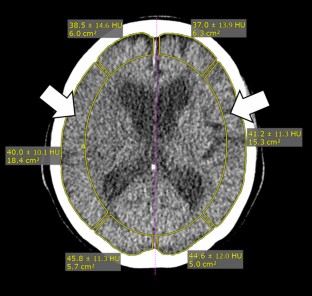

Comparison of a Bayesian estimation algorithm and singular value decomposition algorithms for 80-detector row CT perfusion in patients with acute ischemic stroke

A variety of postprocessing algorithms for CT perfusion are available, with substantial differences in terms of quantitative maps. Although potential advantages of a Bayesian estimation algorithm are suggested, direct comparison with other algorithms in clinical settings remains scarce. We aimed to compare performance of a Bayesian estimation algorithm and singular value decomposition (SVD) algorithms for the assessment of acute ischemic stroke using an 80-detector row CT perfusion.

CT perfusion data of 36 patients with acute ischemic stroke were analyzed using the Vitrea implemented a standard SVD algorithm, a reformulated SVD algorithm and a Bayesian estimation algorithm. Correlations and statistical differences between affected and contralateral sides of quantitative parameters (cerebral blood volume [CBV], cerebral blood flow [CBF], mean transit time [MTT], time to peak [TTP] and delay) were analyzed. Agreement of the CT perfusion-estimated and the follow-up diffusion-weighted imaging-derived infarct volume were evaluated by nonparametric Passing–Bablok regression analysis.

CBF and MTT of the Bayesian estimation algorithm were substantially different and showed a better correlation with the standard SVD algorithm (ρ = 0.78 and 0.80, p < 0.001) than with the reformulated SVD algorithm (ρ = 0.59 and 0.39, p < 0.001). There is no significant difference in MTT only when using the reformulated SVD algorithm (p = 0.217). Regarding the regression lines, the slope and intercept were nearly ideal with the Bayesian estimation algorithm (y = 2.42 x-6.51; ρ = 0.60, p < 0.001) in comparison with the SVD algorithms.

The Bayesian estimation algorithm can lead to a better performance compared with the SVD algorithms in the assessment of acute ischemic stroke because of better delineation of abnormal perfusion areas and accurate estimation of infarct volume.